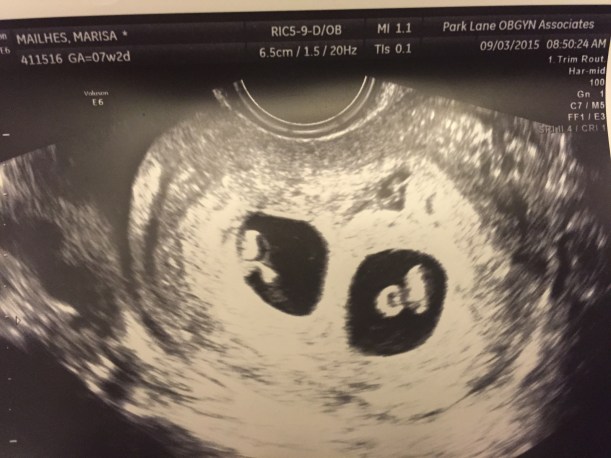

image1Baby A is on the left, Baby B is on the right.

We walk into the sonogram room and the tech says “lets see how many babies are in there” and laughs. I barely hear her because I am so nervous and even when I realize what she said I brush it off because its not even a thought in my head. Colbie is parked in her stroller right in front of the monitor that shows everything and Trey is sitting next to me. I have my eyes covered because I just cannot handle the thought of bad news. The tech BARELY starts the sonogram and says “Oh! There ARE two in there!” I immediately uncover my eyes and see the unmistakable picture of twins. (I didn’t actually know what twins would look like that early on, but when you see it on the sonogram you just KNOW its twins). Colbie giggles and looks up at me and then I look at Trey. Biggest eyes you’ve ever seen! He can’t speak and I just start laughing. I am so relieved that there is nothing wrong, so relieved there actually is a baby in there (omg there’s 2 in there!) and so unbelievably in shock that I can’t do a single thing, but laugh.

img_0823